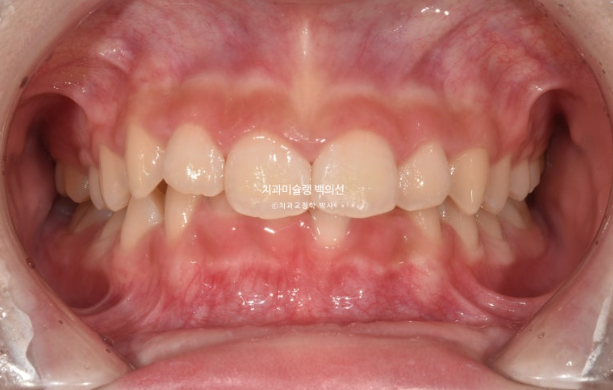

교정치료를 위해 내원한 중학생 친구입니다.

앞니 높낮이 차이가 눈에 띕니다.

가운데 앞니 두개가 내려와 토끼이처럼 보입니다.

윗니가 아랫니를 과하게 덮어 아랫니가 보이지 않을 정도입니다.

과개교합 이라고 합니다.

인비절라인 모더레이트의 적응증인 상태이지만 이 당시에는 모더레이트 포르그램이 런칭 되기 전이였습니다.